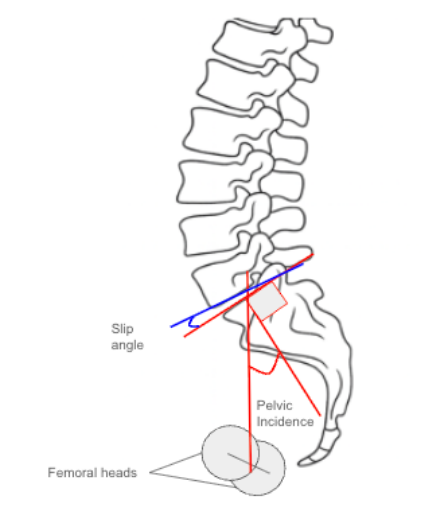

2) Instructions to Measure

• Obtain a standing lateral lumbosacral X-ray including the pelvis, sacrum, and L5 vertebra.

• Identify key anatomic landmarks:

• Center of the femoral heads (midpoint if both visible).

• Center of the S1 superior endplate.

• Inferior endplate of L5 and superior endplate of S1.

• Measure Pelvic Incidence (PI):

• Draw a line connecting the center of the femoral heads to the center of the S1 endplate.

• Draw a line perpendicular to the S1 endplate.

• The angle between these two lines is the Pelvic Incidence (PI).

• Measure Slip Angle (Lumbosacral Kyphosis Angle):

• Draw a line along the inferior endplate of L5.

• Draw a line along the superior endplate of S1.

• Measure the angle between these lines, which represents the Slip Angle.

• Assess the Relationship:

• Compare PI and Slip Angle values.

• Larger PI–Slip Angle correlation indicates greater lumbosacral kyphosis and pelvic retroversion as compensatory mechanisms.

• Record both measurements (in degrees) and document the alignment classification according to pelvic balance type (see below).